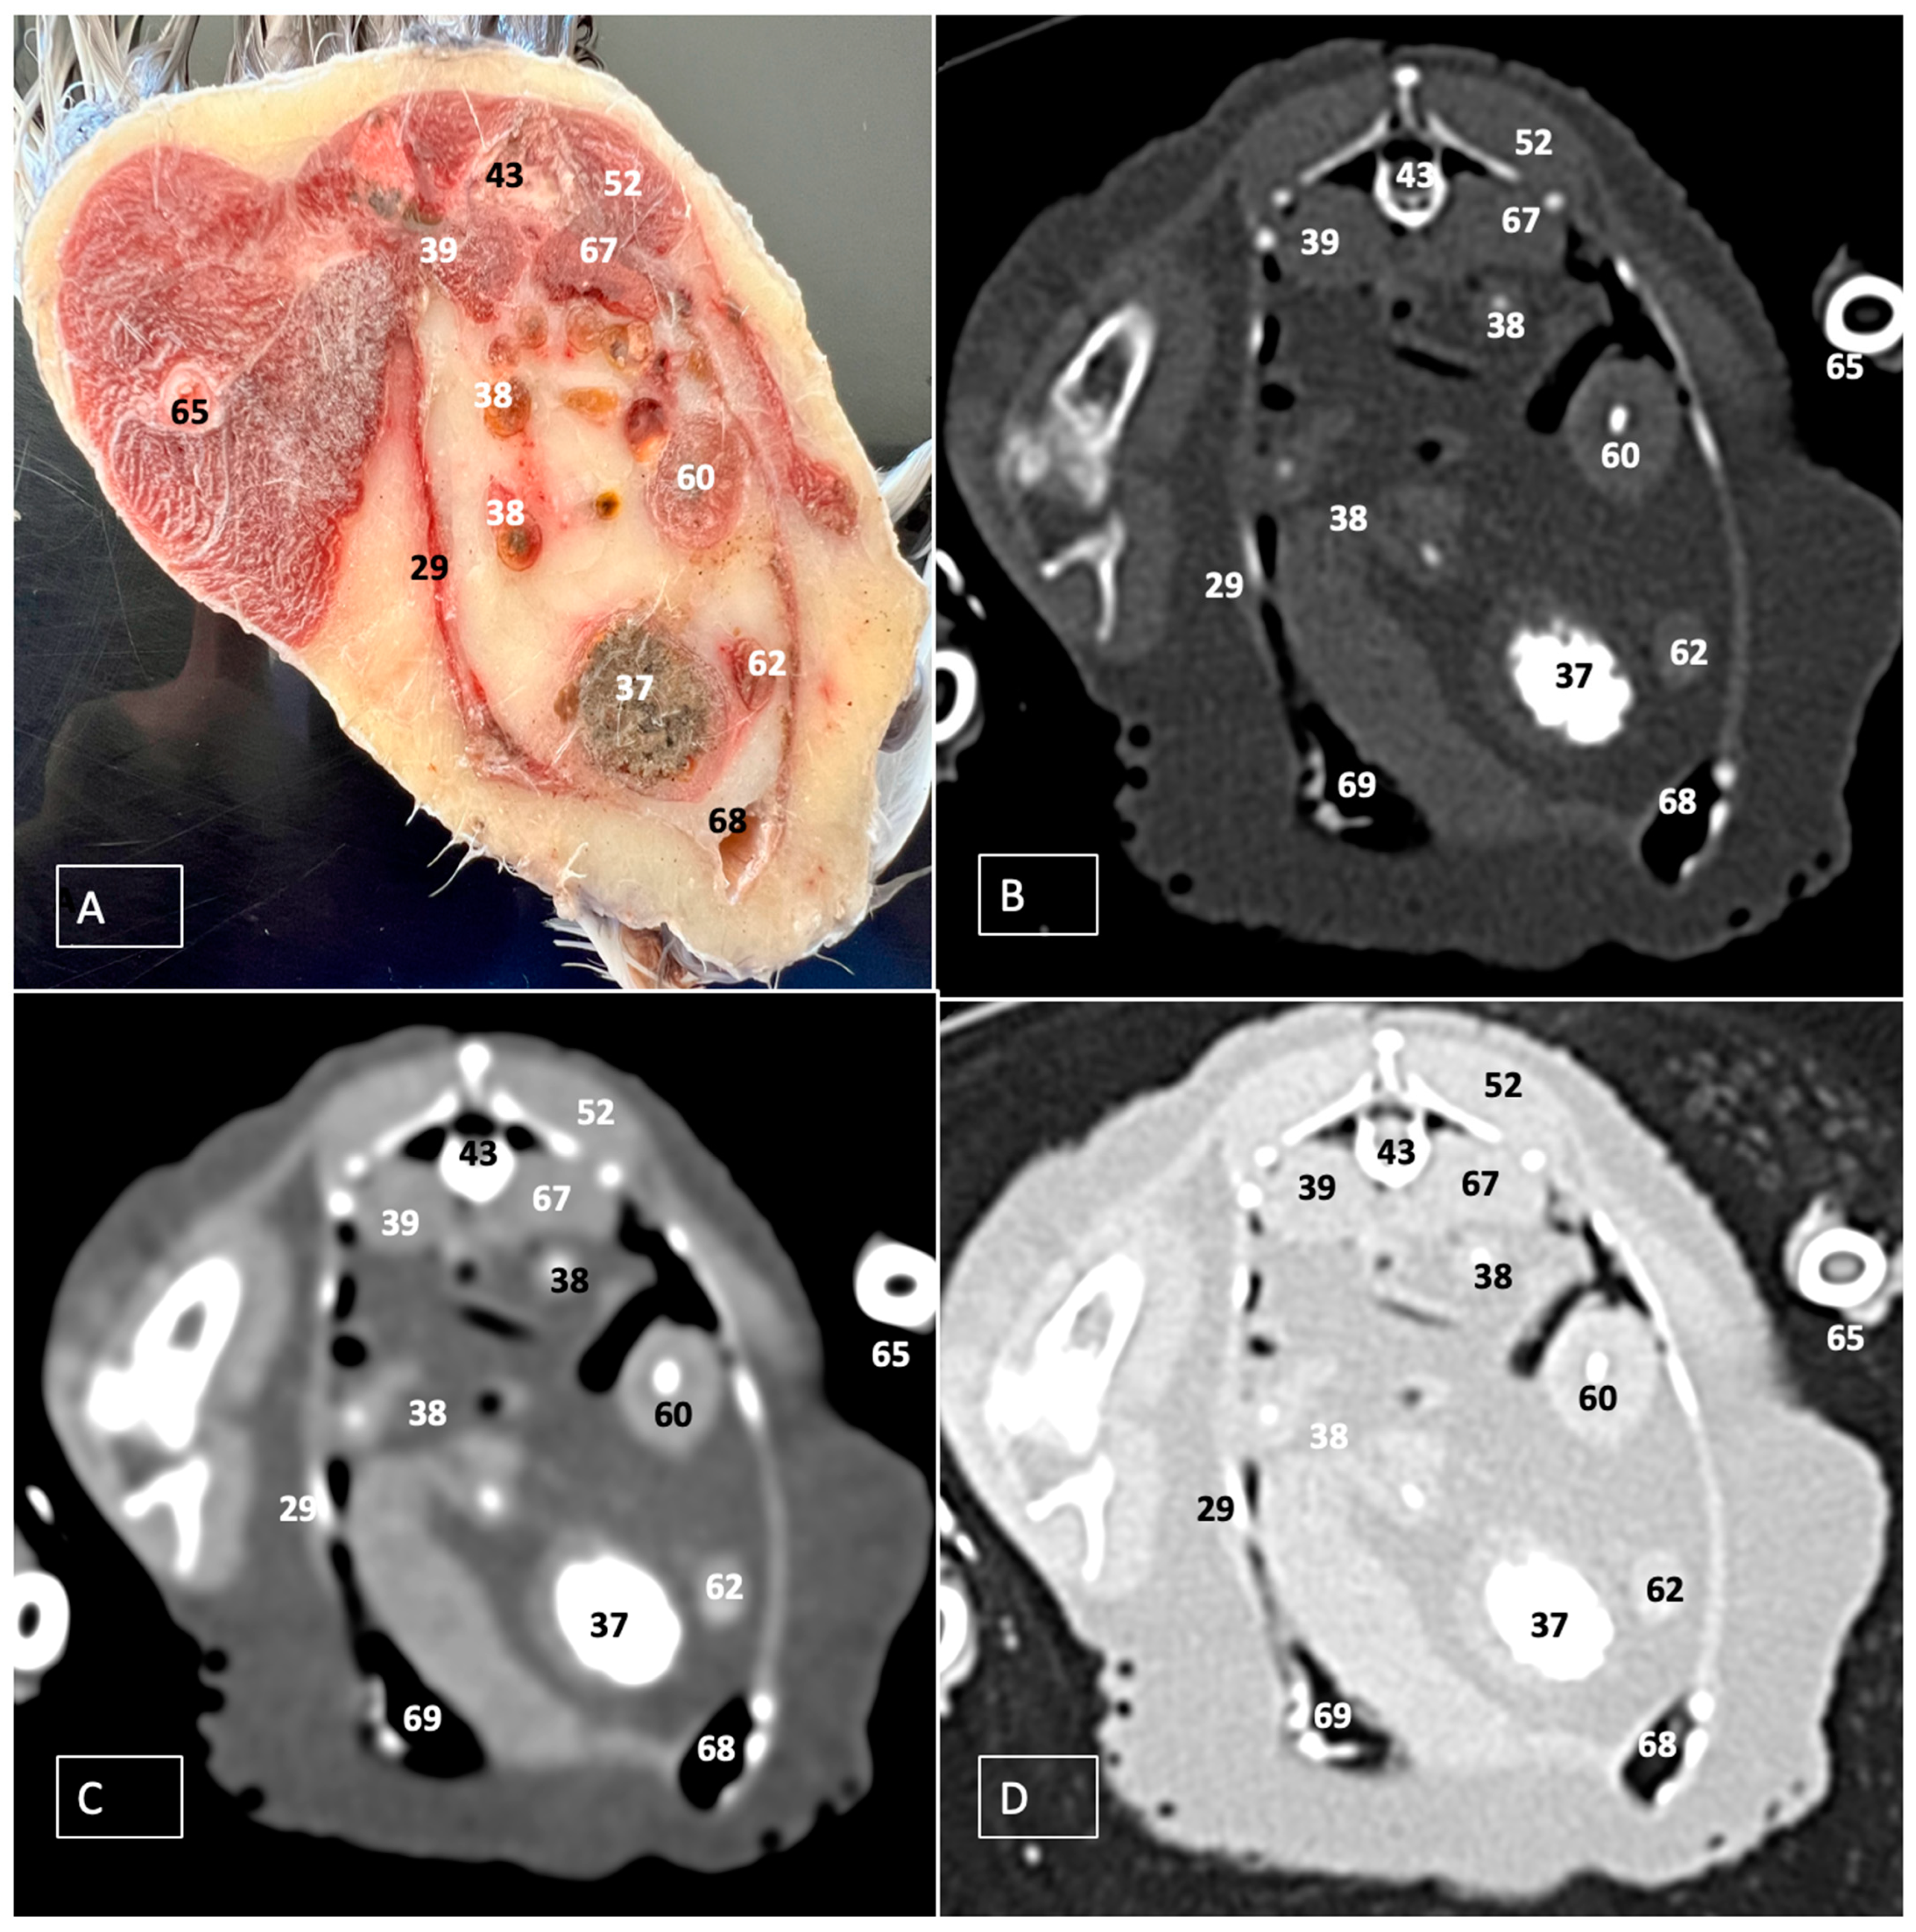

3. Results

3.1. Anatomical Dissections and Cross-Sections

3.2. Computed Tomography Images